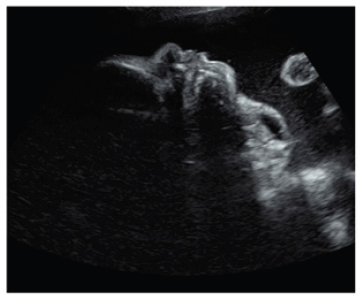

Ultrasound diagnosis has proved to be successful at very early stages of gestation. Thus between the 15-17 weeks an ultrasound detection can be achieved [8,9]. However, most of the lesions are seen in the late second and third trimesters, suggesting that the tumor can develop later in pregnancy [10]. The usonographic diagnostic clusters are based on the display of an anterior or bidirectional organoid facial mass that is partly solid and partly cystic (Figure 1). This mass protrudes (usually with no calcifications) from the fetal mouth and causes hyperextension of the head. Three-dimensional ultrasound can support the prenatal diagnosis [11]. Together with antenatal MRI, three-dimensional ultrasound may thus be of critical importance in identifying fetuses that require an ex utero intrapartum treatment (EXIT) procedure (Figure 1).